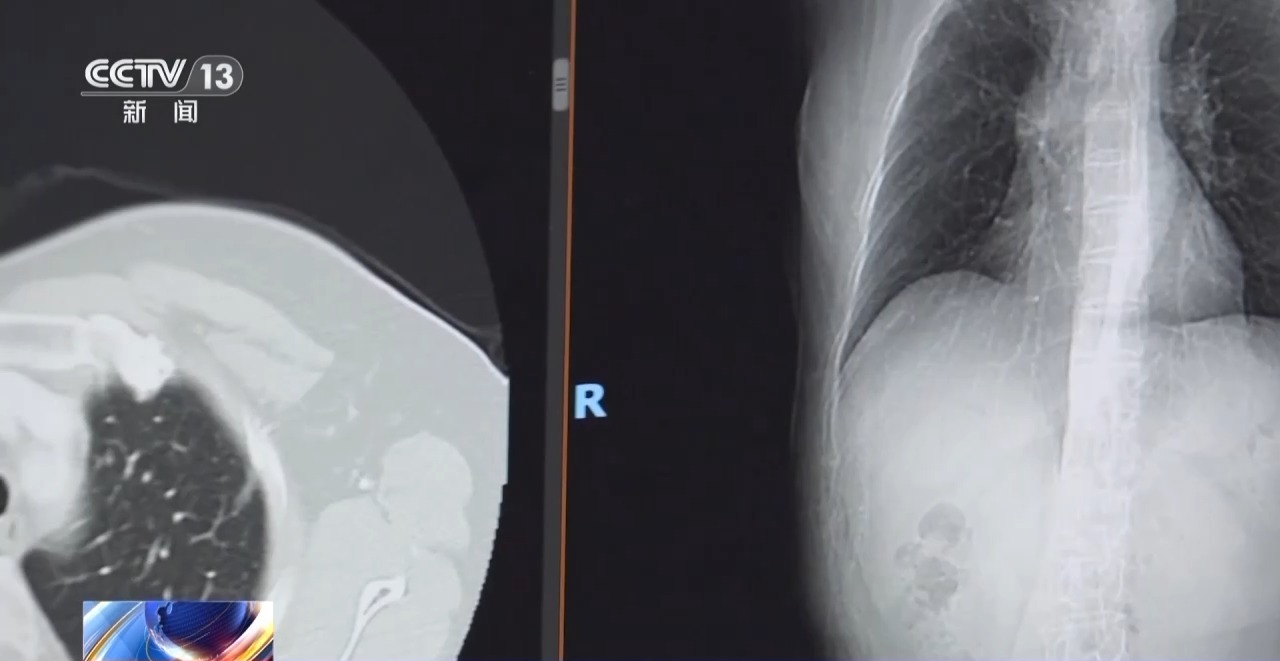

专家表示,肺癌早期通常无症状,2012年以前,我国主要是通过拍胸片进行筛查,近年来,低剂量螺旋CT的普及可将肺癌早期检出率提升至90%。

我国目前推广社区CT筛查肺癌,北京一些区域已将肺癌筛查纳入慢性病管理,覆盖人群超百万。专家同时强调,低剂量螺旋CT有辐射,非高危人群不用每年进行CT筛查,即便是发现肺部有磨玻璃样结节,也切莫过度紧张,按需就诊即可。

北京大学肿瘤医院胸外一科主任 陈克能:对那些非高危的人群,即便是低剂量螺旋CT看见了小结节,我们也要分如下的情况,如果是一个纯磨玻璃样结节,简单说没有实性成分,就不要过度惊慌;如果结节位置不在胸膜下,又不在叶间裂,这些大可不必紧张,没有必要每一年做一次CT。